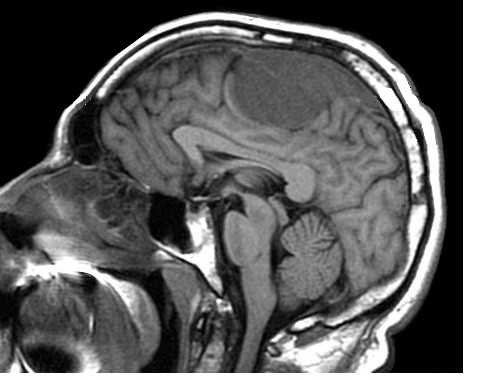

(а) МРТ, FLAIR, аксиальный срез: у женщины 25 лет с «винным пятном» на левой части лица определяются участки повышения сигнала, повторяющие ход извилин левой теменно-затылочной области (симптом «плюща»).

(б) МРТ, постконтрастное Т1 -ВИ, режим подавления сигнала от жира, аксиальный срез: у той же пациентки определяется протяженная пиальная ангиома. Обратите внимание на увеличение размеров ипсилатерального сосудистого сплетения.